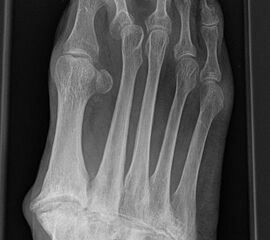

Es gibt neben der Möglichkeit mit der in situ TMT II, III Arthrodese auch die Möglichkeit Fehlstellungen wie den Pes metatarsus adductus zu adressieren (Abb. 9 und Abb. 24 zeigen das prä- und postoperative Röntgenbild eines Patienten mit Pes adductus Korrektur).

• Röntgenkontrolle nach 8-10 Wochen, dann - je nach knöchernem Durchbau - Übergang zur Vollbelastung im Konfektionsschuh (Abb. 24 und 25).

Beispiel Lisfranc Arthrodese bei posttraumatischer Arthrose

Zum Lesen der Bildbeschreibung und zur Vollansicht bitte die Bilder anklicken. Bilder: C. Hase